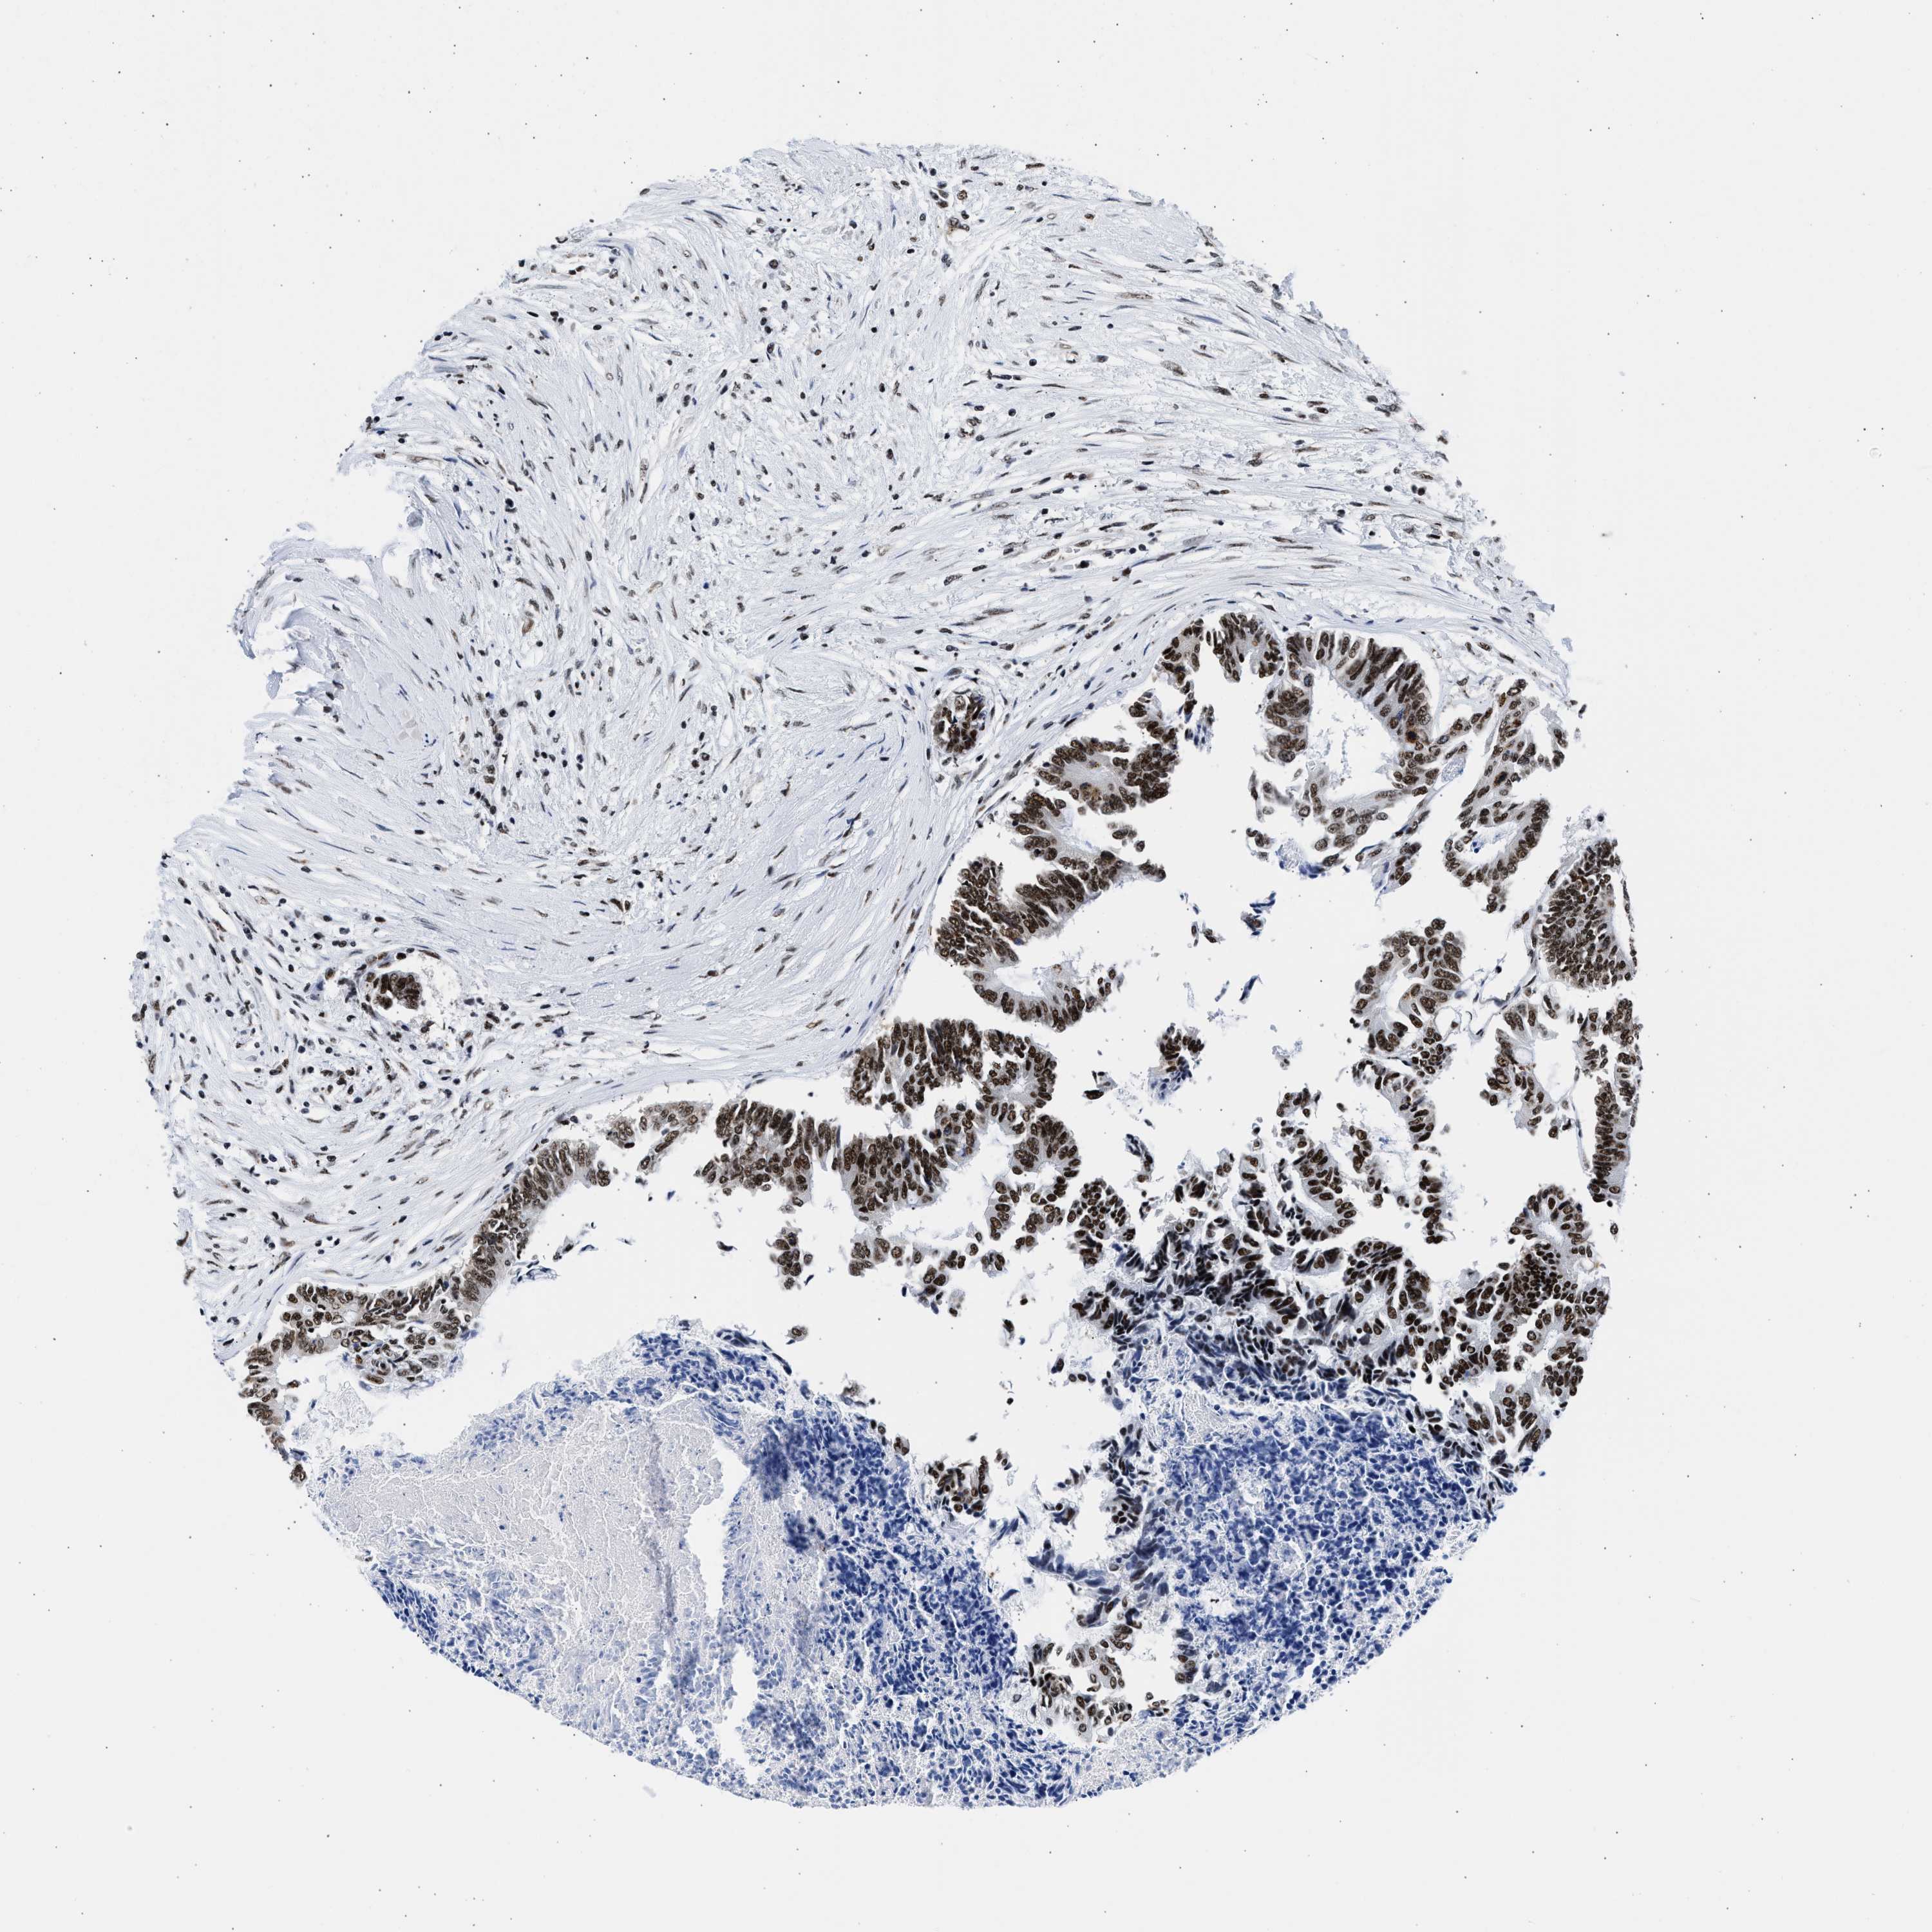

CANCER COLORECTAL CANCER Show tissue menu

Colorectal cancer

Human cancer

Rectum adenocarcinoma